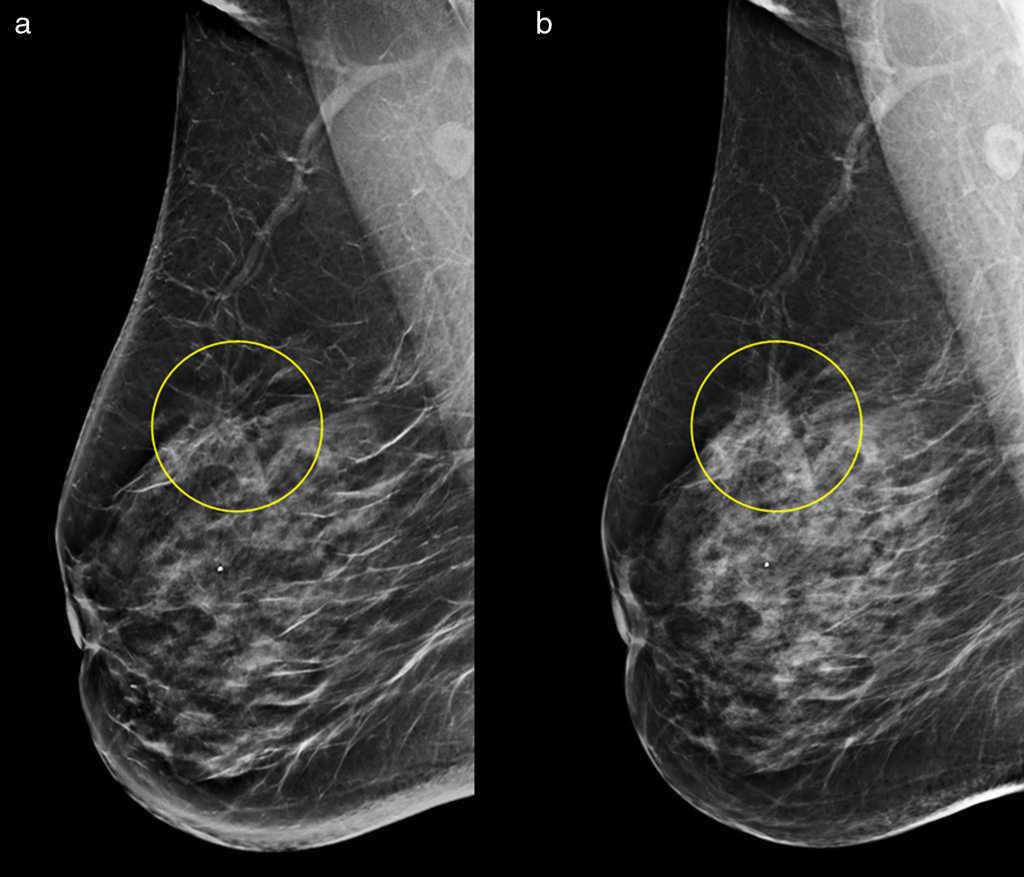

WebDiferencia entre la ecografía mamaria y las mamografías Las mamografías son la técnica que más se utiliza para detectar de forma precoz el cáncer de mama. Este tipo de. WebDiferencias entre la ecografía mamaria y la mamografía . La mamografía es la técnica de diagnóstico por imagen que utiliza rayos X. Se trata del único método.

WebLa mamografía y la ecografía de mama son exámenes diferentes y complementarios que ayudan a detectar la existencia de células cancerígenas en etapas iniciales y por esto es. WebPor su parte, la mamografía toma una imagen de la mama con rayos X, como una radiografía. A diferencia de la ecografía es un proceso un poco molesto, porque el pecho. WebLa mamografía y la ecografía mamaria son las dos técnicas de diagnóstico por imágenes más frecuentes para el estudio de las mamas. Ambos estudios se. WebLa ecotomografía mamaria es un examen complementario a la mamografía, que a través del uso de ondas sonoras ayuda en la detección precoz del cáncer de. WebEste tipo de pruebas diagnósticas suelen tener un precio elevado y la lista de espera interminable. Normalmente el precio de la mamografía oscila entre 150 y 250 euros en.

WebEn español, este estudio de rayos X de las mamas es denominado mastografía. Por otro lado, en inglés se le conoce como “mamography”, razón por la. WebExisten varias imágenes para evaluar la mama, las más comunes son la ecografía mamaria y la mamografía. Diferencias entre Mamografía y Ecografía de seno Autora: Dra.